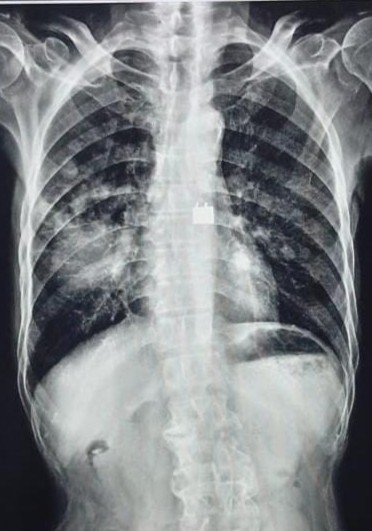

| 207 | IGGMC, Nagpur, Nagpur | P2 | 29-4265 | SHUBHAM MARATHE | Consent taken on Paper | 27 Yrs. |

Provisional Diag : LEFT SIDED CLINICALLY DIAGNOSED PLEURAL EFFUSION

Final Diag : LEFT SIDED CLINICALLY DIAGNOSED TUBERCULAR EMPYMA ON ATT FROM 9.11.2024 |

TB Case (Confirmed) | LEFT SIDED CP ANGLE BLUNTING | Abnormality visible on x-ray |